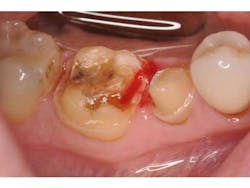

After removal of the provisional restorations, the restorations are tried in and assessed for fit. Although this step is necessary, it will contaminate the intaglio surface of the restorations with moisture and bacteria and thus decrease final bond strength.(5) Before application of silane, the intaglio surface should be cleaned with solution to remove any surface contamination before application of silane (Fig. 3). Studies have shown that a proprietary solution (Ivoclean, Ivoclar) is more effective than water or phosphoric acid gel at restoring precontamination conditions of zirconium oxide. (6) An unpublished internal study revealed similar results for lithium disilicate. (7)